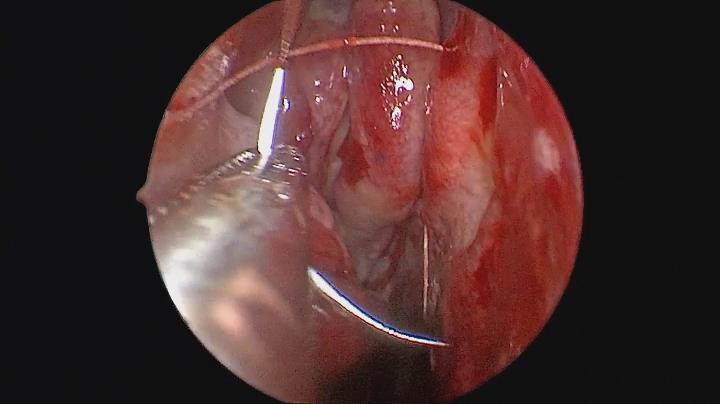

朋友,你是否曾感到一側(cè)的鼻子不通氣?偏頭痛?曾經(jīng)有反復(fù)鼻出血?這有可能是鼻中隔偏曲的表現(xiàn)之一。 鼻中隔偏曲是耳鼻喉科的常見多發(fā)病,發(fā)病率達到15%以上。主要臨床表現(xiàn)為鼻通氣不平衡導(dǎo)致的鼻塞、偏曲嵴突壓迫性引發(fā)的頭痛、氣流沖擊不勻?qū)е卤浅鲅?,并可因為阻塞引流而引發(fā)鼻竇炎。鼻中隔偏曲的最佳治療方案就是做鼻內(nèi)鏡下的鼻中隔矯正手術(shù)。一個成功的鼻中隔矯正術(shù),可以完美的解決偏曲所導(dǎo)致的一系列臨床癥狀。 但是,我們都聽說過一句話:前途是光明的,但道路是曲折的,同樣,鼻中隔手術(shù)效果雖然良好,但是術(shù)后感受卻是不盡人意,至少絕大部分患者術(shù)后反映如此。因為在鼻中隔手術(shù)中需要剝離起雙側(cè)的粘骨膜,矯正或切除偏曲骨質(zhì),之后就需要用填塞材料緊緊塞入雙側(cè)鼻腔進行壓迫,才能夠使分離開的粘骨膜貼敷在一起生長。全麻時候如美夢中的填塞操作雖然讓人渾然不覺,但是清醒后連續(xù)兩天兩夜的鼻塞頭痛、口干舌燥就如同夢魘般讓人痛苦不堪了。 我們耳鼻喉科醫(yī)生對于病人的痛苦感同身受,這促使我們尋找能夠替代鼻中隔術(shù)后填塞的方法,讓患者呼吸順暢、告別夢魘。就在今年,我們開展了鼻中隔縫合術(shù)來替代鼻腔填塞術(shù)。鼻中隔縫合術(shù)是在內(nèi)窺鏡下使用精細針線采取“之”字貫穿法,在鼻中隔粘骨膜兩側(cè)形成“川”字形縫線,并用同一根線縫合切口,通過縫線的錨定作用,將雙側(cè)粘骨膜牢牢地貼敷在一起,而避免了填塞的痛苦??p線一般在5天拆除后患者就可以出院了,比之前還縮短了2天的住院時間。 經(jīng)過對填塞法和縫合法的兩類患者恢復(fù)情況的觀察,填塞法術(shù)后不僅感受痛苦,而且因為嬌嫩的鼻腔粘膜經(jīng)過48小時的壓迫刺激,術(shù)后粘膜腫脹時間較長、分泌物較多,鼻通暢恢復(fù)較慢,反之,縫合法患者可以在術(shù)后第一天就可以享受通暢的呼吸,而且沒有惱人的鼻子脹、腦袋痛、嘴巴干。另外,更重要的是,鼻中隔縫合術(shù)后患者無一例發(fā)生鼻中膈血腫、穿孔等并發(fā)癥。 我科開展鼻中隔縫合術(shù)在全國范圍屬于前列,據(jù)我們了解,部分醫(yī)院雖然也開展了此方法,但是因為諸多擔(dān)心依舊使用明膠海綿、納西棉等柔軟的可吸收材料進行填塞,雖然沒有了鼻脹頭痛,但是仍舊無法經(jīng)鼻呼吸,依然口干舌燥。 非填塞的鼻中隔縫合術(shù),終于讓患者徹底擺脫夢魘般痛苦,享受順暢的呼吸!